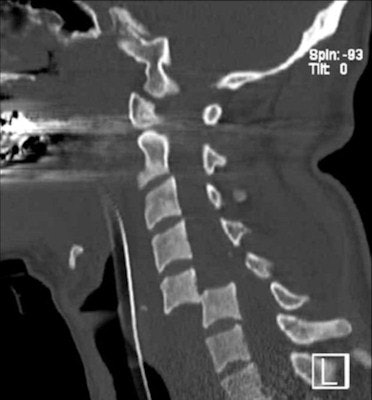

CT volumetric representation of a complex amputation injury of the right lower extremity due to trauma sustained from road traffic accident. Image courtesy of Dr. Stefan Wirth.